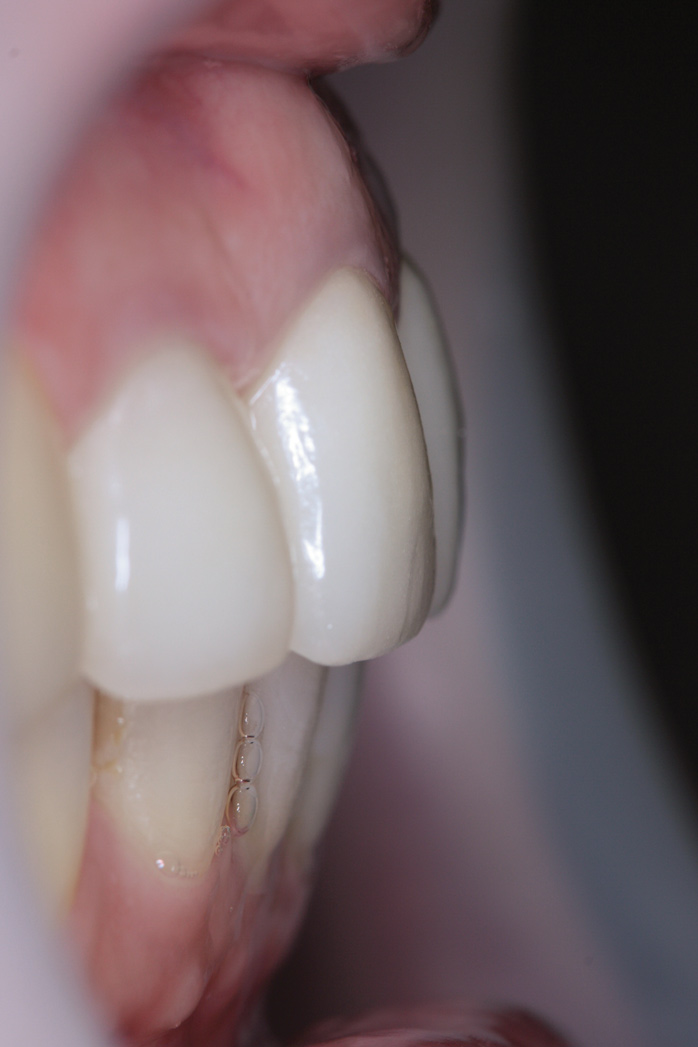

Fig 8. Increased VDO through use of temporary crown on No. 19 implant.

Figure 8